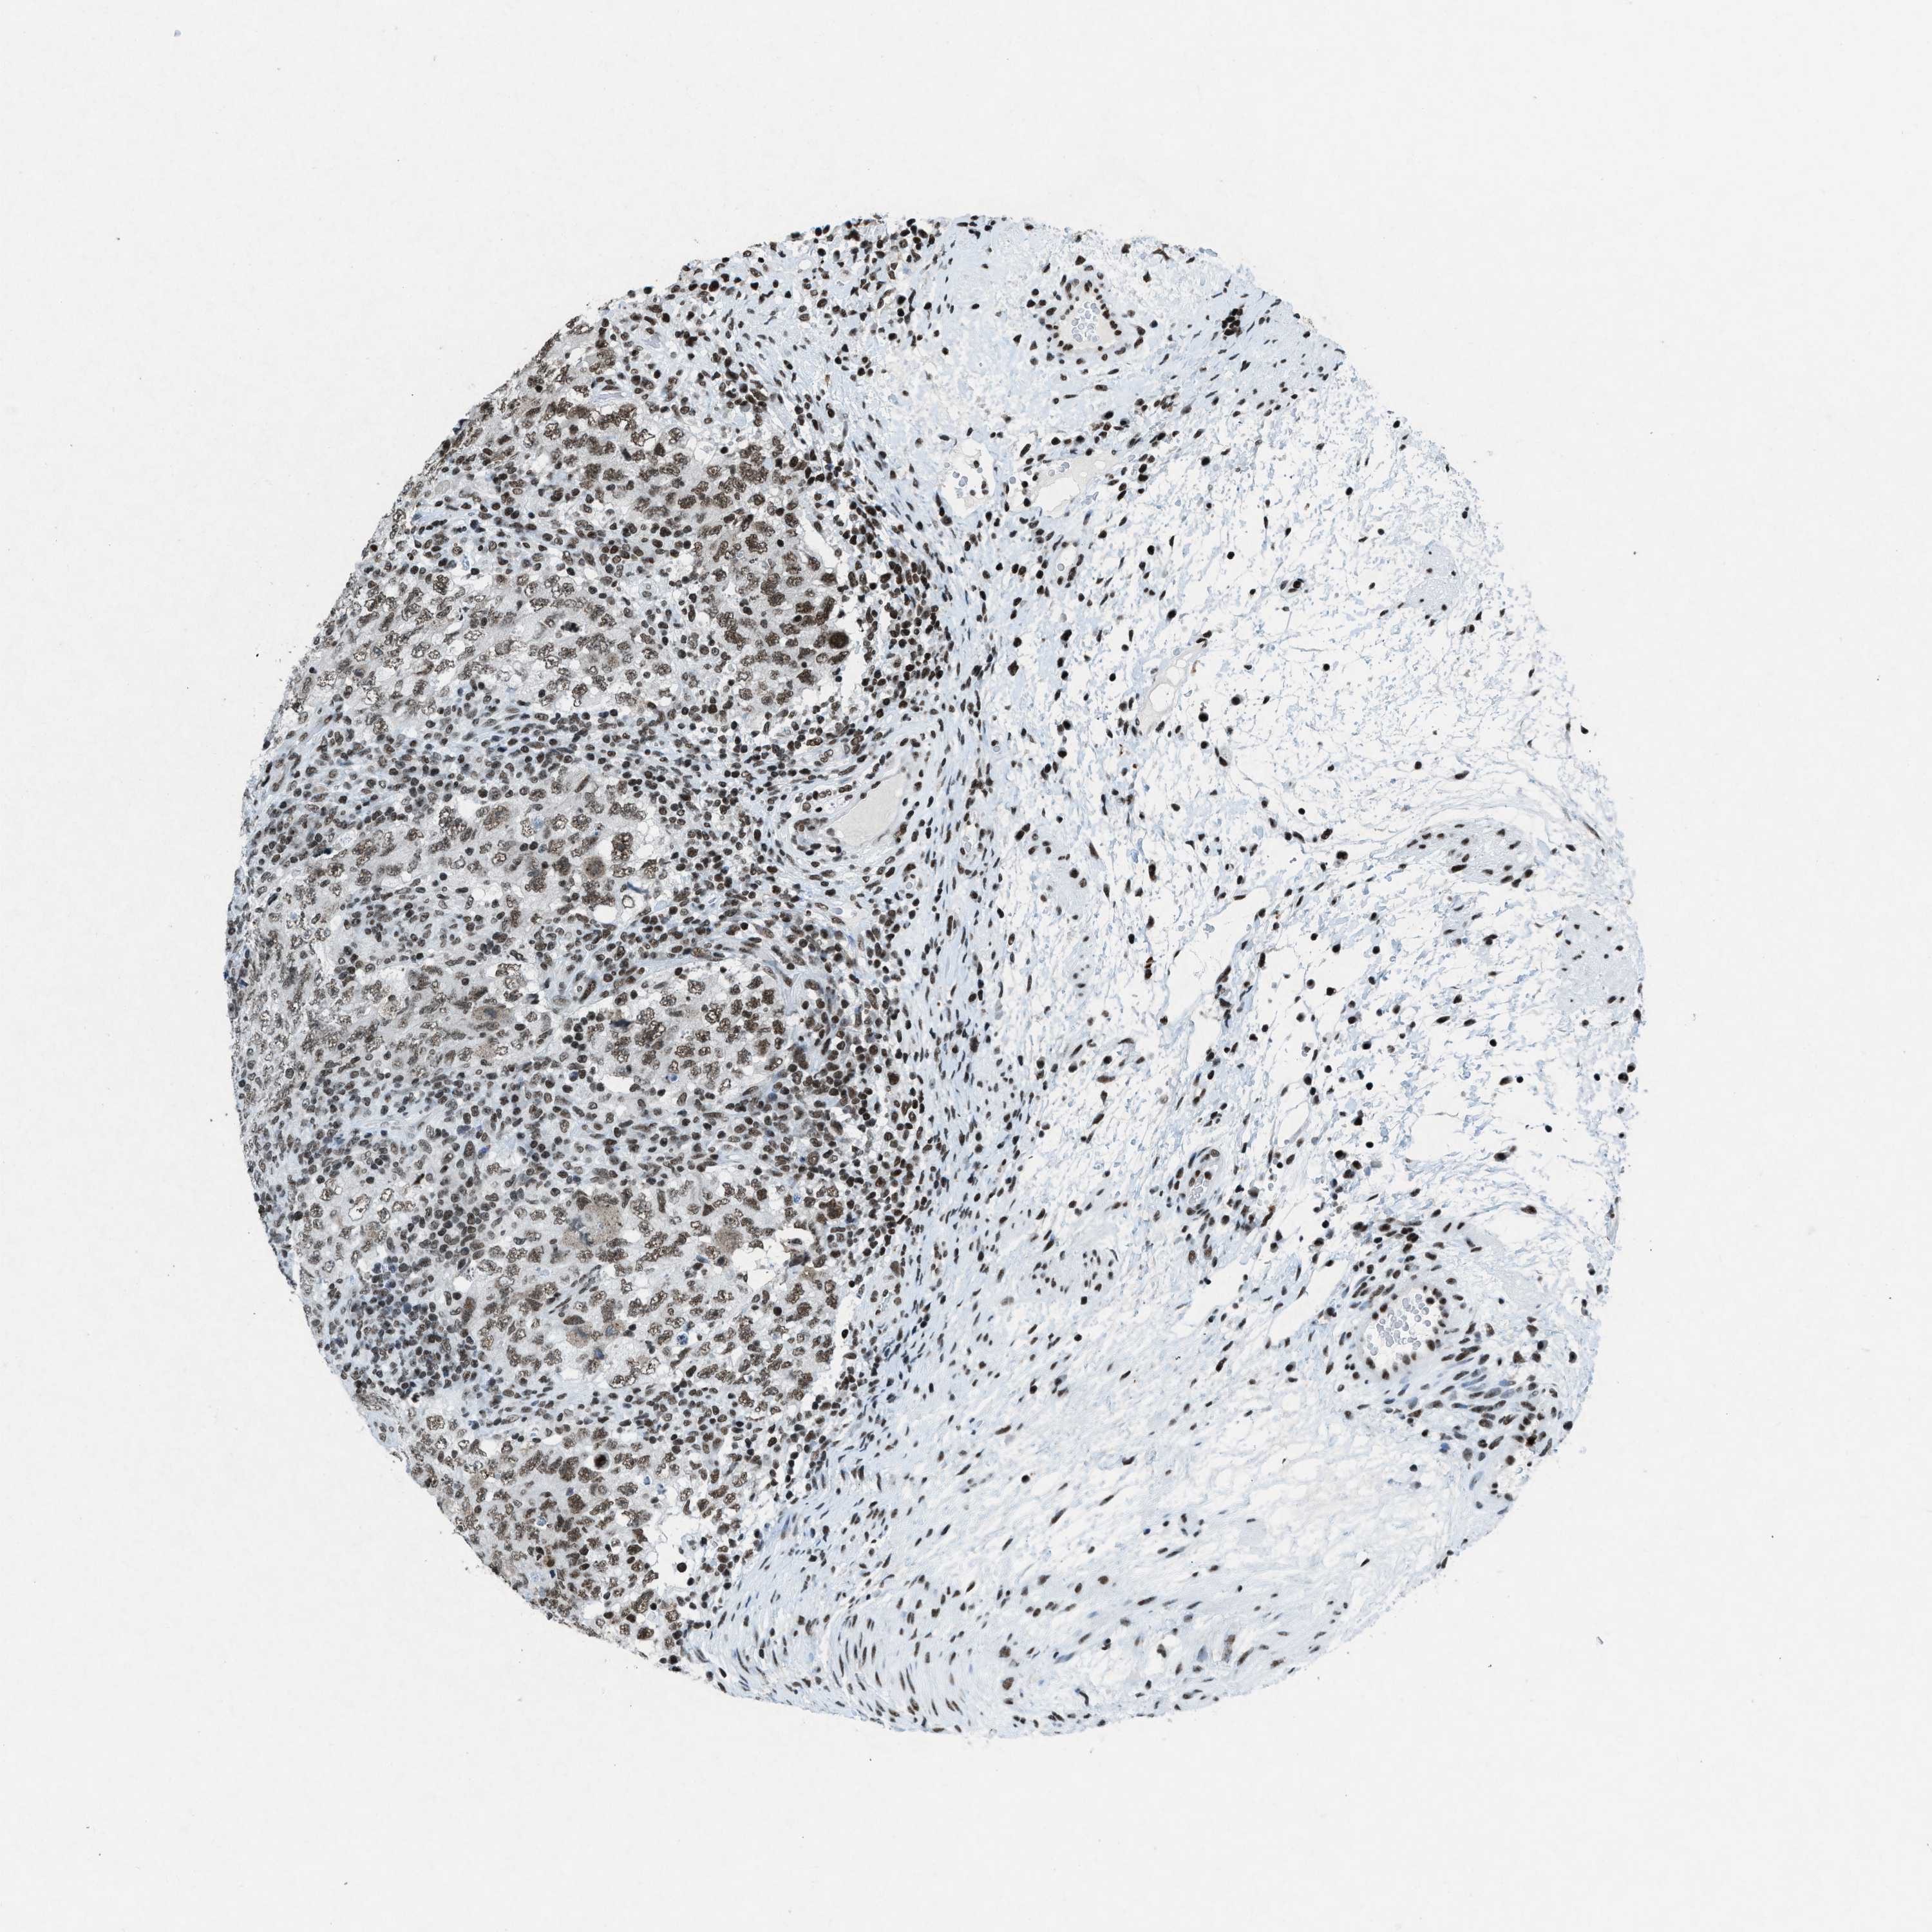

TESTIS CANCER - Protein expressioni

A mouse-over function shows sample information and annotation data. Click on an image to view it in a full screen mode. Samples can be filtered based on level of antibody staining by selecting one or several of the following categories: high, medium, low and not detected. The assay and annotation is described here.

Note that samples used for immunohistochemistry by the Human Protein Atlas do not correspond to samples in the TCGA dataset.

Antibody stainingi

Antibody staining in the annotated cell types in the current human tissue is reported as not detected, low, medium, or high, based on conventional immunohistochemistry profiling in selected tissues. This score is based on the combination of the staining intensity and fraction of stained cells.

Each image is clickable and will lead to virtual microscopy that enables deeper exploration of all samples and also displays staining intensity scores, fraction scores and subcellular localization as well as patient and tissue information for each sample.

Antibody HPA061593

Antibody CAB016327

Staining

High

Medium

Low

Not detected

Intensity

Strong

Moderate

Weak

Negative

Quantity

>75%

75%-25%

<25%

None

Location

Nuclear

Cytoplasmic/membranous

Cytoplasmic/membranous,nuclear

Seminoma, NOS

Carcinoma, Embryonal, NOS